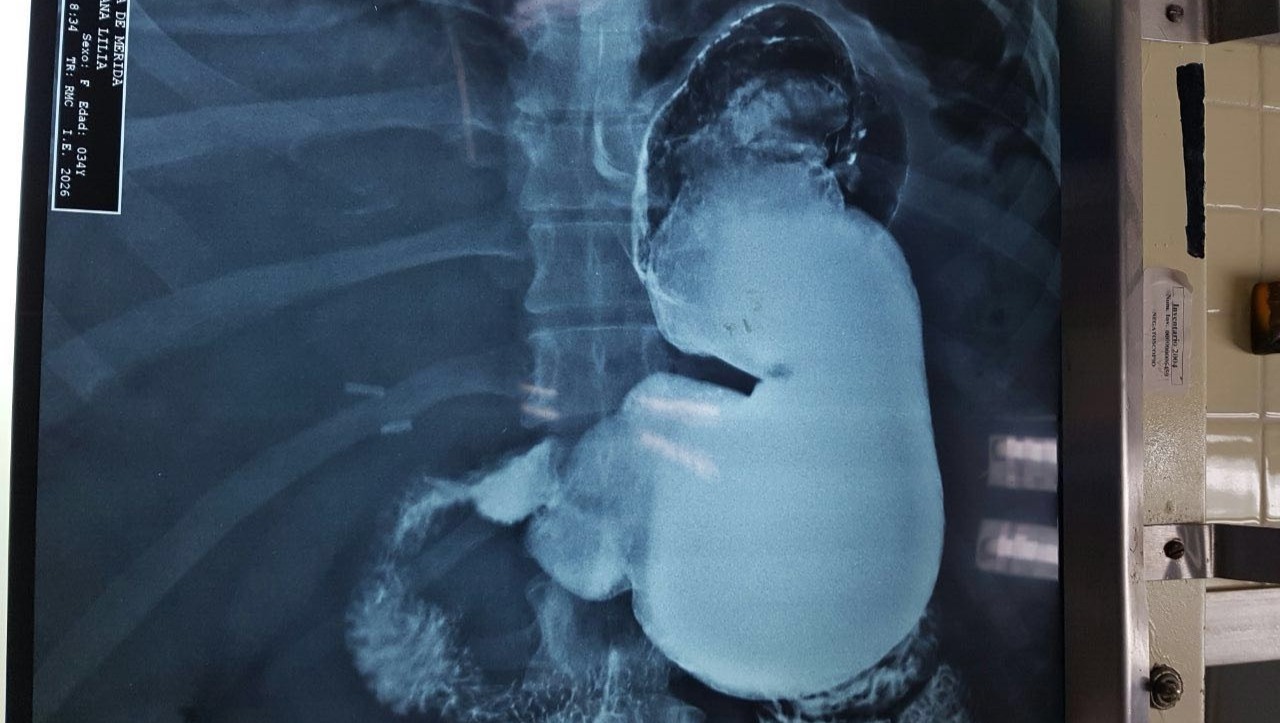

video Una Segunda Oportunidad de Vida MI ESTOMAGO POCOS MESES DESPUES DE LA MALA CIRUGIA QUE ME REALIZARON.

Hola, me llamo Ana Lilia, soy una mujer joven con muchas ganas de vivir y salir adelante. Quisiera tener la libertad de valerme por mi misma, salir a la calle, convivir con amigos, familia. Necesito operarme lo más pronto posible de un bypass gástrico, pues hace unos años me hicieron una mala cirugía la cual me dejó una deuda enorme, y muchos problemas de salud (hipotiroidismo, hipertensión, colesterol, diabetes, ginecológicos, una hernia, entre otros). Y sobre todo ese doctor con su mala praxis y ambición jugó con lo más sagrado: la vida y muchas ilusiones depositadas en esta operación. Actualmente peso 200 kilos y desgraciadamente me ha incapacitado.